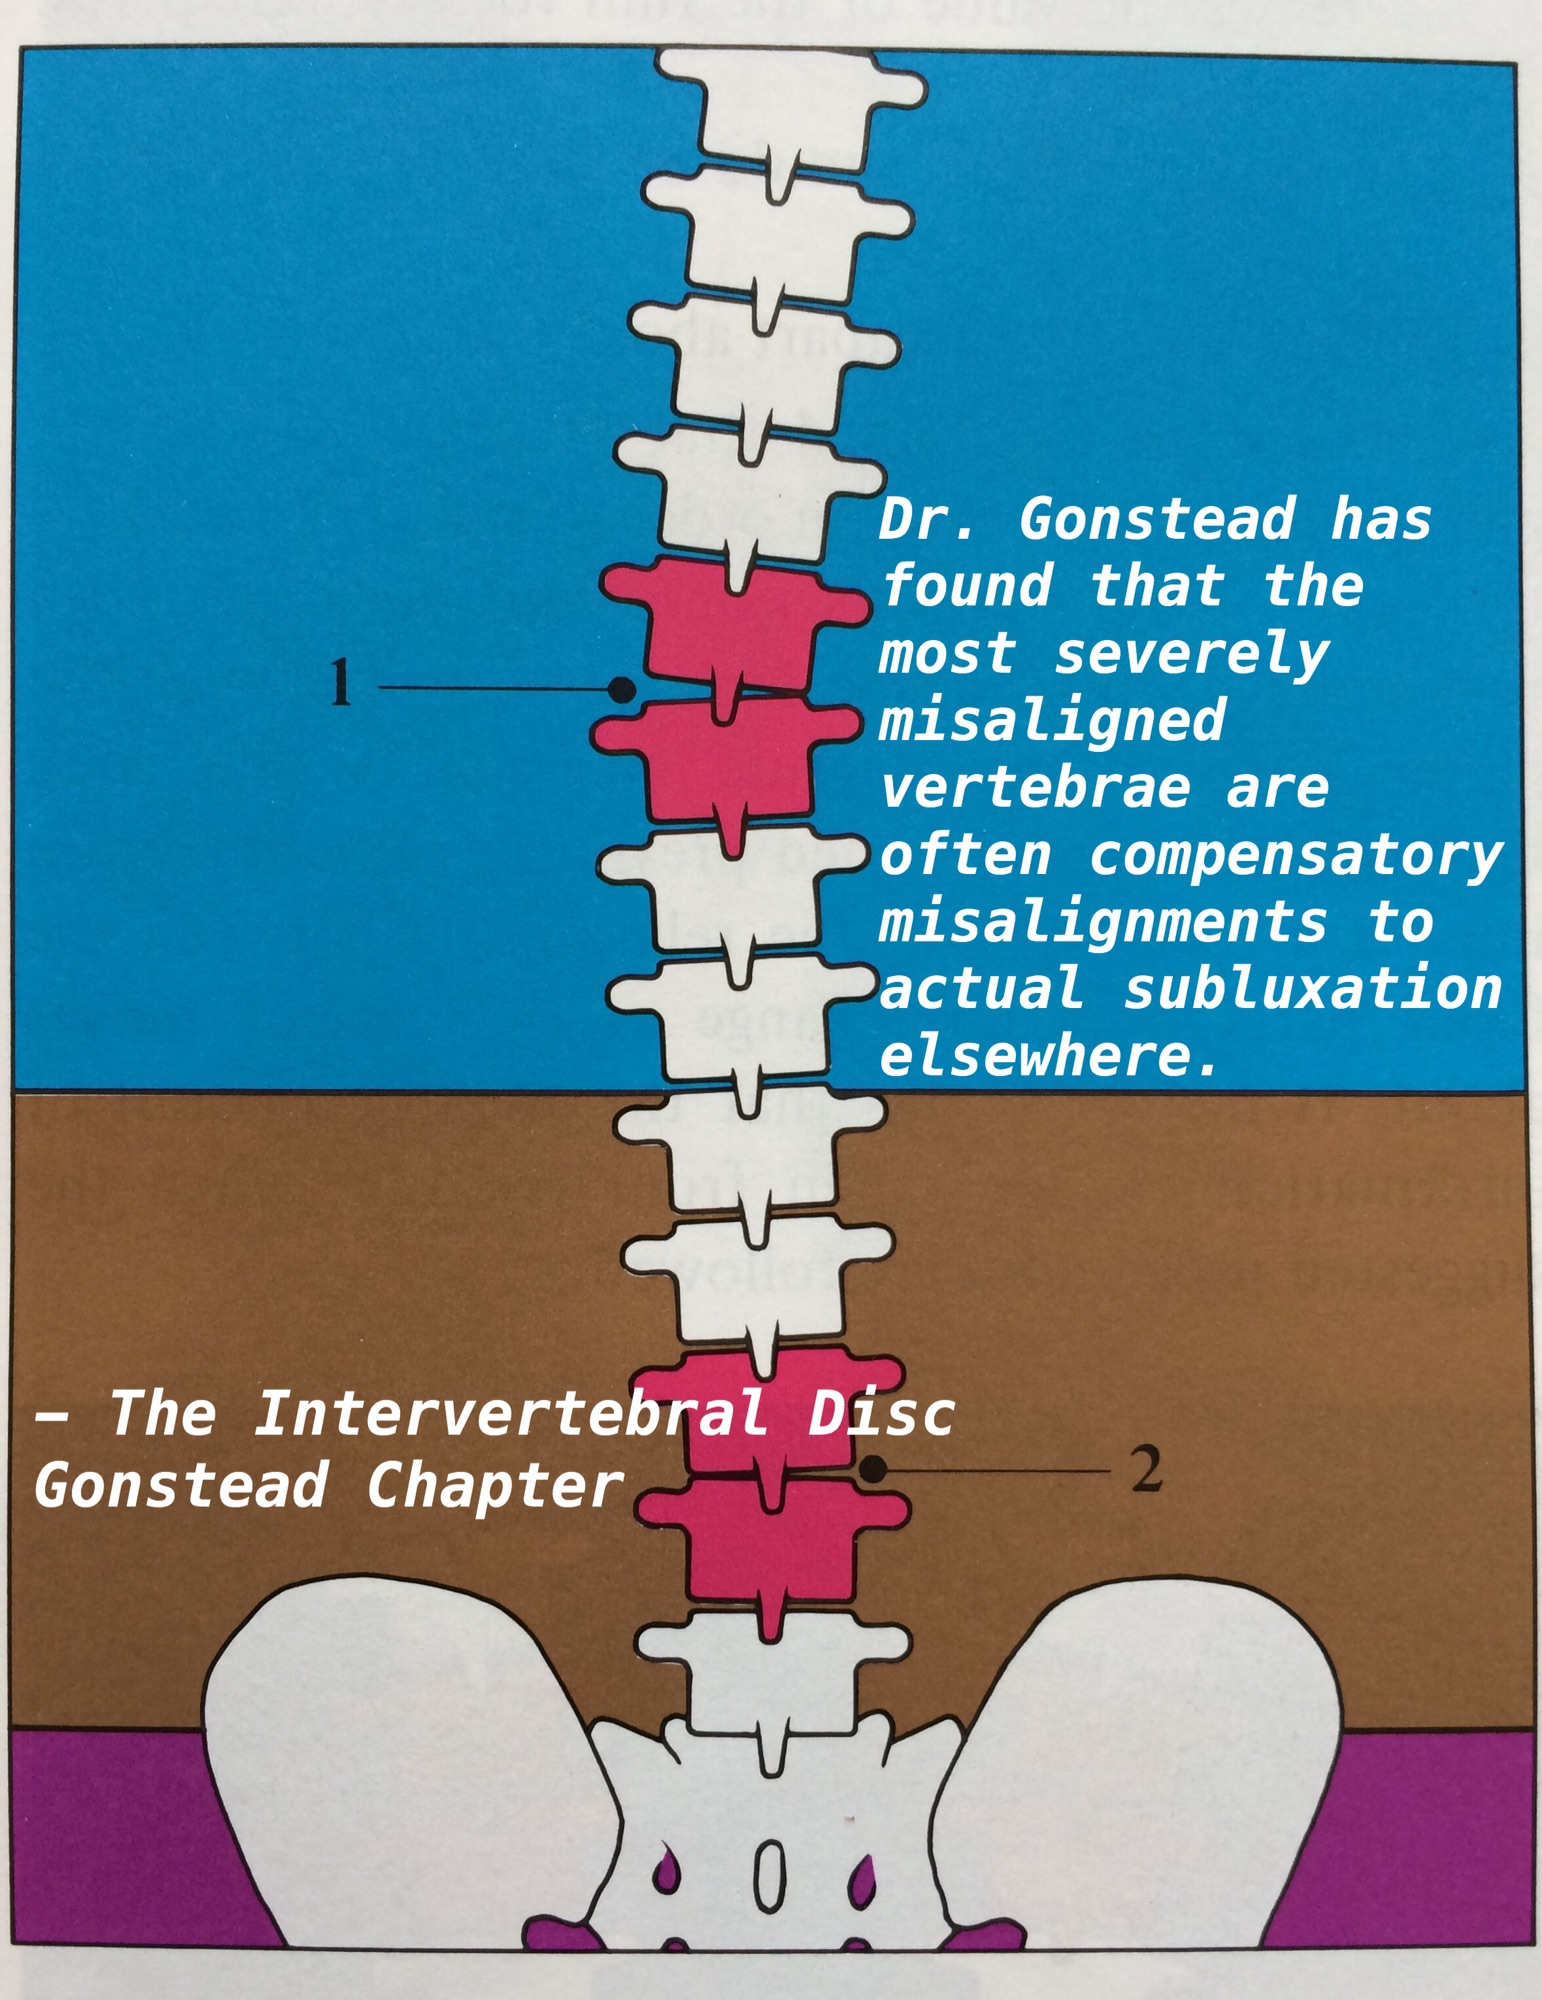

1番悪そうに見えても、そうとは限らない

1番悪そうに見えても、そうとは限らない

Compensation

Compensation